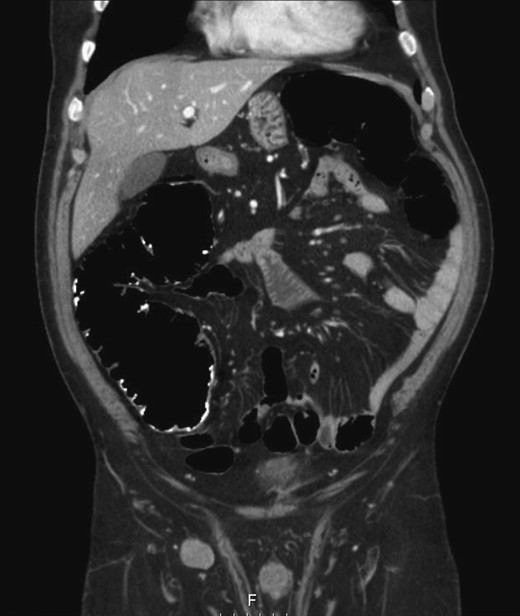

The patient remained in follow-up for 2 years with no evidence of recurrence by CT and colonoscopy. After 2 years, endoscopic evaluation became impossible due to stenosis of colorectal anastomosis (not transposable), requiring the realization of colonography by CT to exclude external compression of the anastomosis. The test showed absence of expansive lesions around the anastomosis, polypoid thickness or abnormal parietal thickness, although it revealed a right inguinal lymphadenopathy with 25 mm (Fig. 1), deserving histological characterization. Fine needle aspirative biopsy concluded that the new lesion represented a colon adenocarcinoma metastasis.

Right inguinal lymphadenopathy in colonography by computerized tomography.